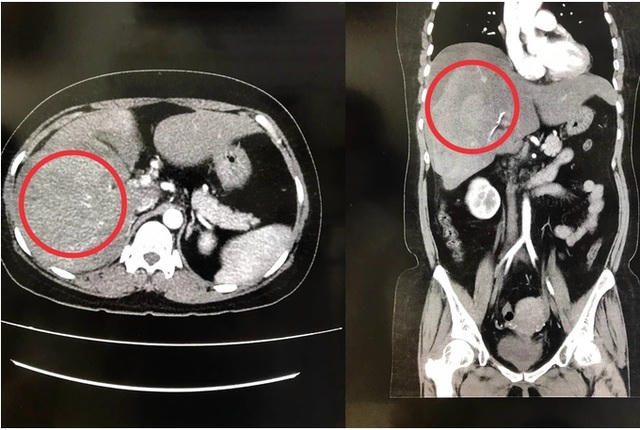

Qua thăm khám, siêu âm và chụp CT-scan bụng, các bác sĩ chẩn đoán bệnh nhân bị dập vỡ gan phải hạ phân thùy V, chảy máu ổ bụng, gây xuất huyết nội rất nguy hiểm. Sau đó bệnh nhân được điều trị nội khoa tích cực, theo dõi sát mạch, huyết áp và tình trạng bụng.

Ảnh chụp CT-scan cho thấy gan phải của chị L bị vỡ. Ảnh: DT |